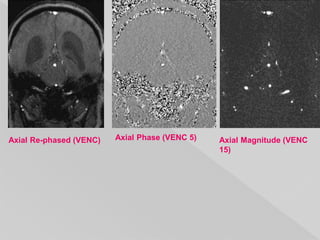

 Images are typically presented in sets of 3 for

each plane and velocity encoding (VENC)

obtained, similar to susceptibility weighted

imaging (SWI). The set comprises of 1:

 re-phased image (magnitude of flow

compensated signal)

› flow is of high signal

› background is visible

 magnitude image (magnitude of difference

signal)

› flow is of high signal (regardless of direction)

› background is suppressed

 phase image (phase of difference signal)

› signal is dependent on direction: forward flow is of

high signal; reverse flow is of low signal

› background is mid-grey

Axial Re-phased (VENC) Axial Phase (VENC 5) Axial Magnitude (VENC

15)